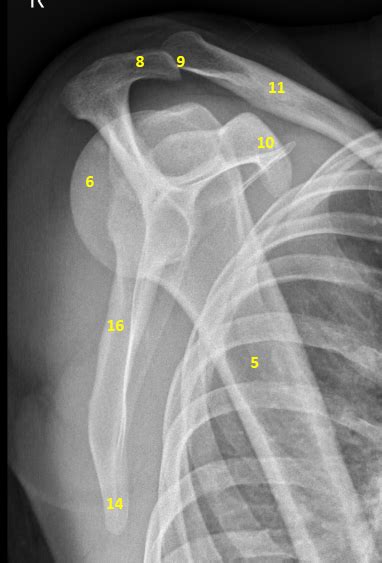

Shoulder: Annotated X-rays | Image | Radiopaedia.org

Shoulder: annotated x-rays | Image | Radiopaedia.org radiopaedia.org

shoulder lateral rays radiopaedia scapula scapular annotated ap anatomy radiology axillary fracture version figure posterior series